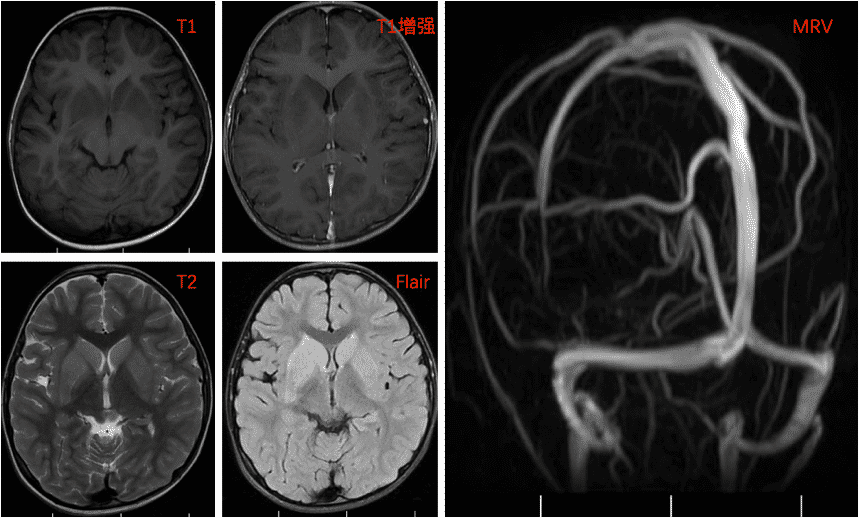

刘x,49岁,突发意识模糊3天

一、病例特点:患者中年男性,急性发病;临床表现为意识水平下降伴认知减退、情感异常、吞咽障碍及二便失禁;既往曾行股骨头置换术,留有左下肢活动欠灵活;吸烟史30年,平均约20支/日,已戒烟1周;饮酒史30年,平均约半斤/日,已戒1周。专科查体:意识模糊,言语稍笨拙,双双眼左视时可见水平粗大眼震,双眼外展均受限,右侧肢体肌力Ⅲ+级,右侧巴氏征阳性,脑膜刺激征阴性,余查体不配合。辅助检查: 肝肾功能+电解质 :总蛋白:63.9g/L,↓;白蛋白(溴甲酚绿法):30.1g/L,↓; 白球比:0.9,↓; 丙氨酸氨基转移酶:113U/L,↑;天冬氨酸氨基转移酶:178U/L,↑;钠:133mmol/L,↓; 氯:98.0mmol/L,↓; 镁:0.74mmol/L,↓; 血常规 :白细胞计数:3.39×10^9/L,↓;红细胞计数:2.81×10^12/L,↓; 血红蛋白量:110g/L,↓; 红细胞比积:0.310,↓;平均红细胞体积:111.4fL,↑; 平均红细胞血红蛋白量:39.10pg,↑; 红细胞分布宽度SD:56.7fL,↑;血小板计数:93×10^9/L,↓维生素B12:>1476pmol/L,↑; 叶酸:5.07nmol/L,↓; 贫血六项:铁蛋白:>2000μg/L,↑;转铁蛋白:1.97g/L,↓; 血清总铁结合力:42.40μmol/L,↓; 铁:8.8μmol/L,↓。二、神经影像头MR(2024-3-17) :双侧丘脑及双侧额叶皮层见多发对称性长T1长T2信号,FLAIR像为高信号,DWI上病变呈高信号影,ADC上病变呈等信号影。 影像结果:双侧丘脑及双侧额叶皮层对称性异常信号,建议进一步检查。 头MRS(2024-3-26):2.02ppmNAA 峰正常(NAA/Cr<1),3.20ppm胆碱峰(Cho)轻度上升(Cho/Cr>1),2.4ppm谷氨酸复合物峰(β,γ-Glx)、3.05ppm肌酸峰(Cr)、3.90ppmCr的第二峰均可明显分辨,未见明显异常。综合表现为:Cho/Cr上升。MRS示双侧丘脑病变区Cho/Cr轻度上升,请结合临床。三、临床诊断:Wernick 脑病Tips 心情驿站